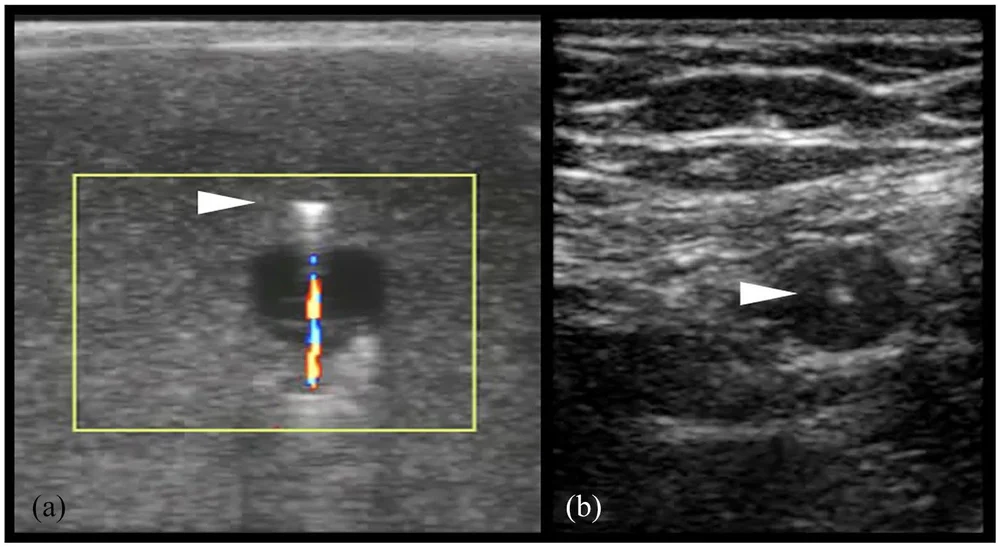

Color Flash Artifact Ultrasound . twinkling artifact is seen with color flow doppler ultrasound 1. Those from violation of ultrasound system assumptions and those from interference. in this review, the ultrasound (us) artifacts features such as propagation path, velocity, attenuation, multiple echoes, and resolution are explained. the colour flash artifact is a commonly encountered artifact on colour doppler ultrasound, representing spurious. for instance, some artifacts may be indicative of certain pathologies. artifacts can be broken down into two categories: flash artifact occurs as a result of motion of the patient or the transducer and presents as a sudden flash of color filling the color box. They are not to be confused with. It occurs as a focus of alternating colors on doppler. understand these artifacts to avoid these misdiagnoses and protect patients from undue intervention. the color flash artifact occurs where movement of the fetus or tissue is erroneously translated to flow, evidenced. The main restrictions of an axial and lateral resolution are artifacts.

RiT radiology Color Doppler Twinkling Artifact Color Flash Artifact Ultrasound They are not to be confused with. in this review, the ultrasound (us) artifacts features such as propagation path, velocity, attenuation, multiple echoes, and resolution are explained. for instance, some artifacts may be indicative of certain pathologies. flash artifact occurs as a result of motion of the patient or the transducer and presents as a sudden flash. Color Flash Artifact Ultrasound.

Color Doppler Twinkling Artifacts in Various Conditions During Color Flash Artifact Ultrasound It occurs as a focus of alternating colors on doppler. in this review, the ultrasound (us) artifacts features such as propagation path, velocity, attenuation, multiple echoes, and resolution are explained. The main restrictions of an axial and lateral resolution are artifacts. twinkling artifact is seen with color flow doppler ultrasound 1. They are not to be confused with.. Color Flash Artifact Ultrasound.